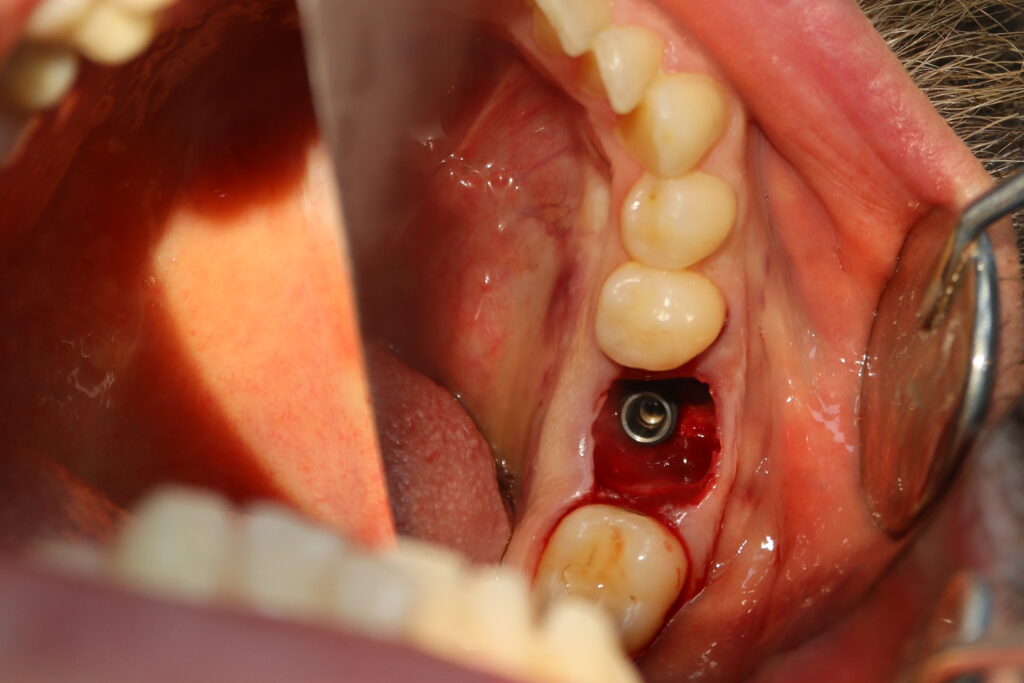

За одно посещение был удален зуб 3.6 и установлен имплантат Megagen AnyOne, установлен формирователь десневой манжетки.

процедура имплантации